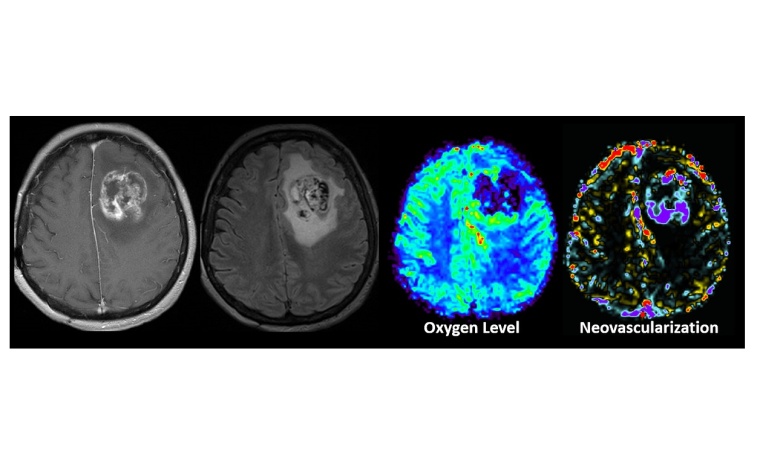

Zum Erreichen ihres beeindruckenden Ergebnisses trainierte das Team neun bekannte Multiclass ML Algorithmen mit MRT-Daten von 167 früheren Patienten, die an einem der fünf häufigsten Hirntumore erkrankt waren und bei denen eine exakte Klassifizierung mittels Histologie vorlag. Dabei wurden in einem aufwendigen Protokoll insgesamt 135 Classifier generiert. Das sind mathematische Funktionen, die eine Zuordnung des zu untersuchenden Materials in bestimmte Kategorien vornehmen. „Im Unterschied zu vorherigen Studien berücksichtigten wir auch Daten von physiologischen MRTs“, erläutert Prof. Stadlbauer. „Dazu zählten Details zur Gefäßarchitektur der Tumore und deren Bildung neuer Gefäße sowie zur Versorgung des Tumorgewebes mit Sauerstoff.“